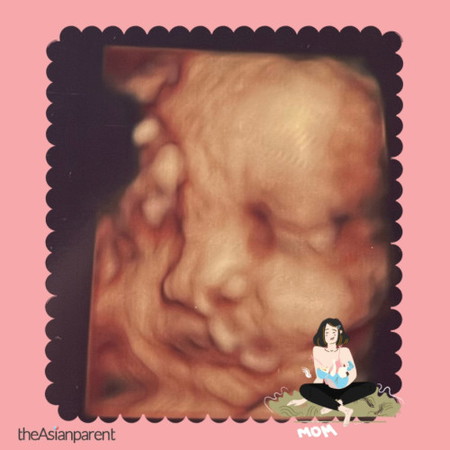

normal ke tali pusat ke tu😢

hi mommy!! nak tanya sikit ni harini baru lepas 5D scan then apa dekat mulut baby tu ea🥲 masa scan 21w takde pun and nampak clear je mulut dia.. Dr kata itu tali pusat tapi kita as #firstmom masih takut dan insecure 😢 now 31w